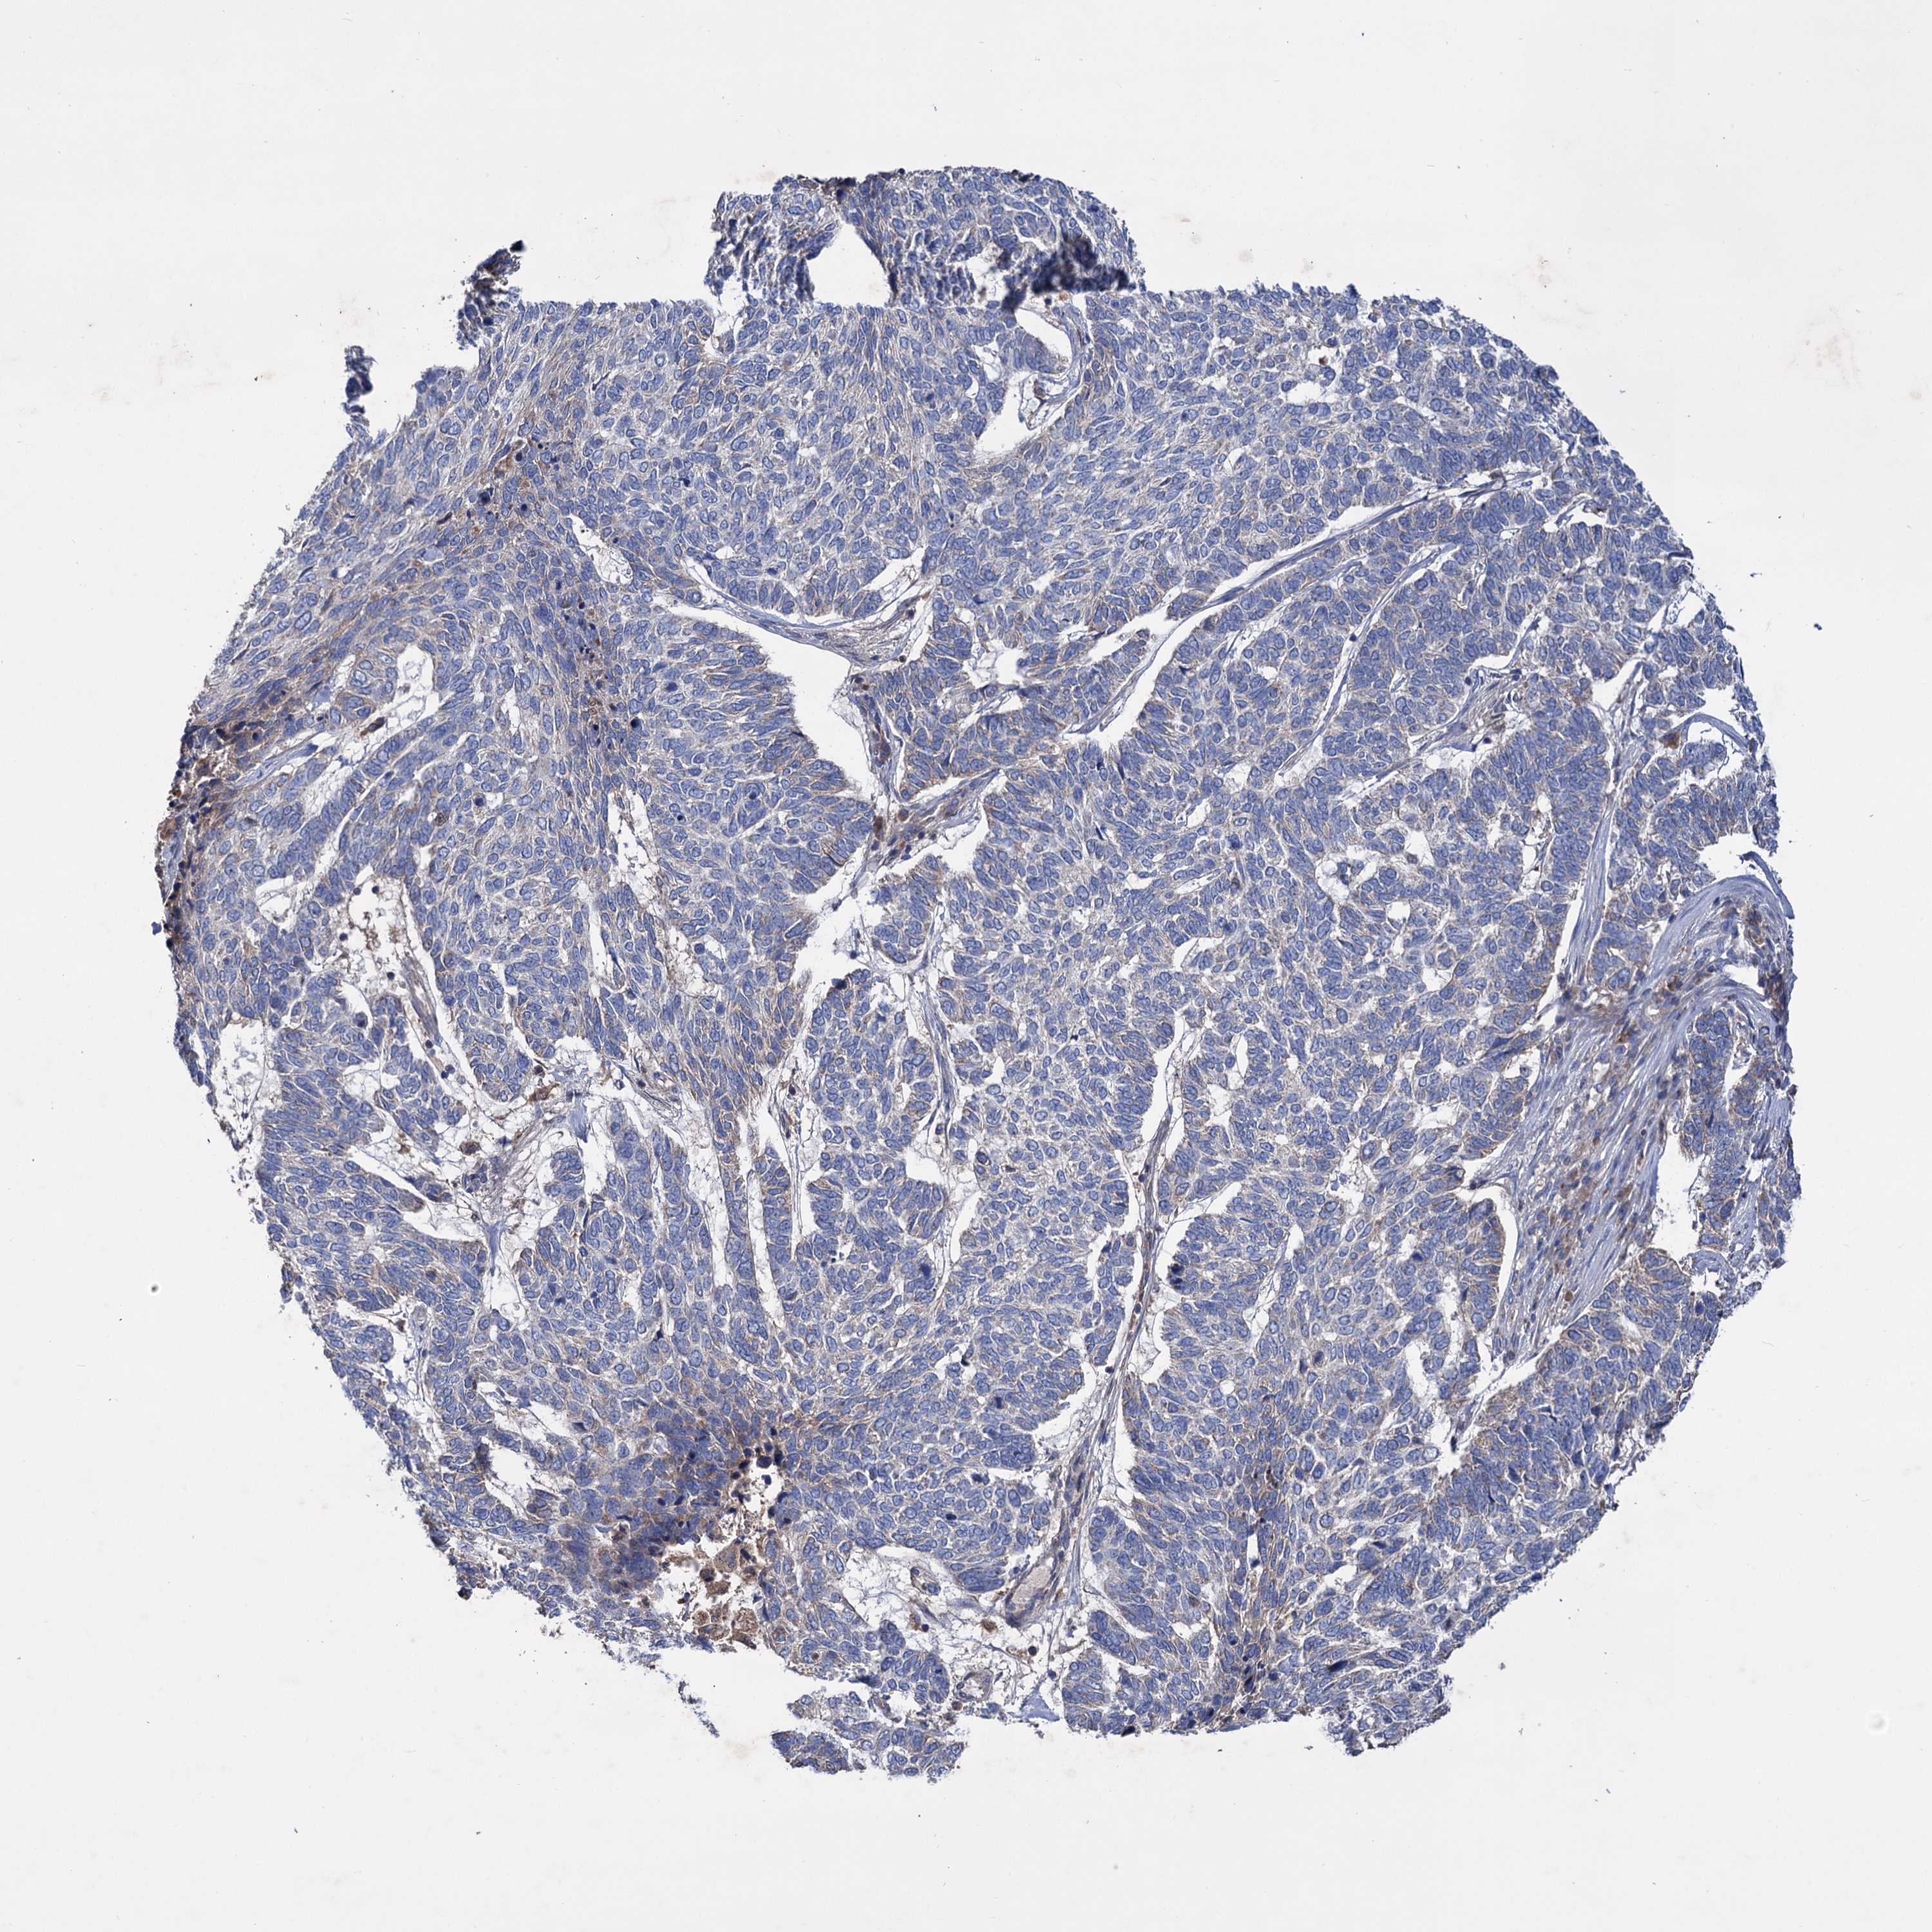

CANCER SKIN CANCER Show tissue menu

Basal cell and squamous cell cancer

SKIN CANCER - Protein expressioni

A mouse-over function shows sample information and annotation data. Click on an image to view it in a full screen mode. Samples can be filtered based on level of antibody staining by selecting one or several of the following categories: high, medium, low and not detected. The assay and annotation is described here.

Each image is clickable and will lead to virtual microscopy that enables deeper exploration of all samples and also displays staining intensity scores, fraction scores and subcellular localization as well as patient and tissue information for each sample.

Antibody HPA039005

Basal cell carcinoma

Squamous cell carcinoma, NOS

Squamous cell carcinoma, metastatic, NOS